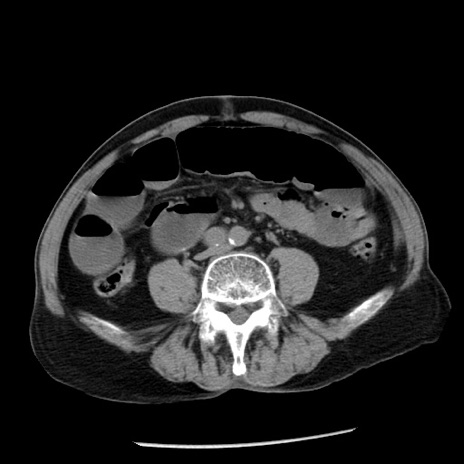

症例26(横断像)

【症例】80歳代男性

【主訴】嘔吐

【現病歴】昨晩2回嘔吐あり、今朝になっても嘔吐あり。来院。

【既往歴】胃潰瘍

【身体所見】意識清明、BT 37.6℃、BP 166/95mmHg、HR 100bpm、SpO2 97%、腹部:平坦・軟、腸蠕動音聴取良好、圧痛なし。

【データ】WBC 21900、CRP 1.46